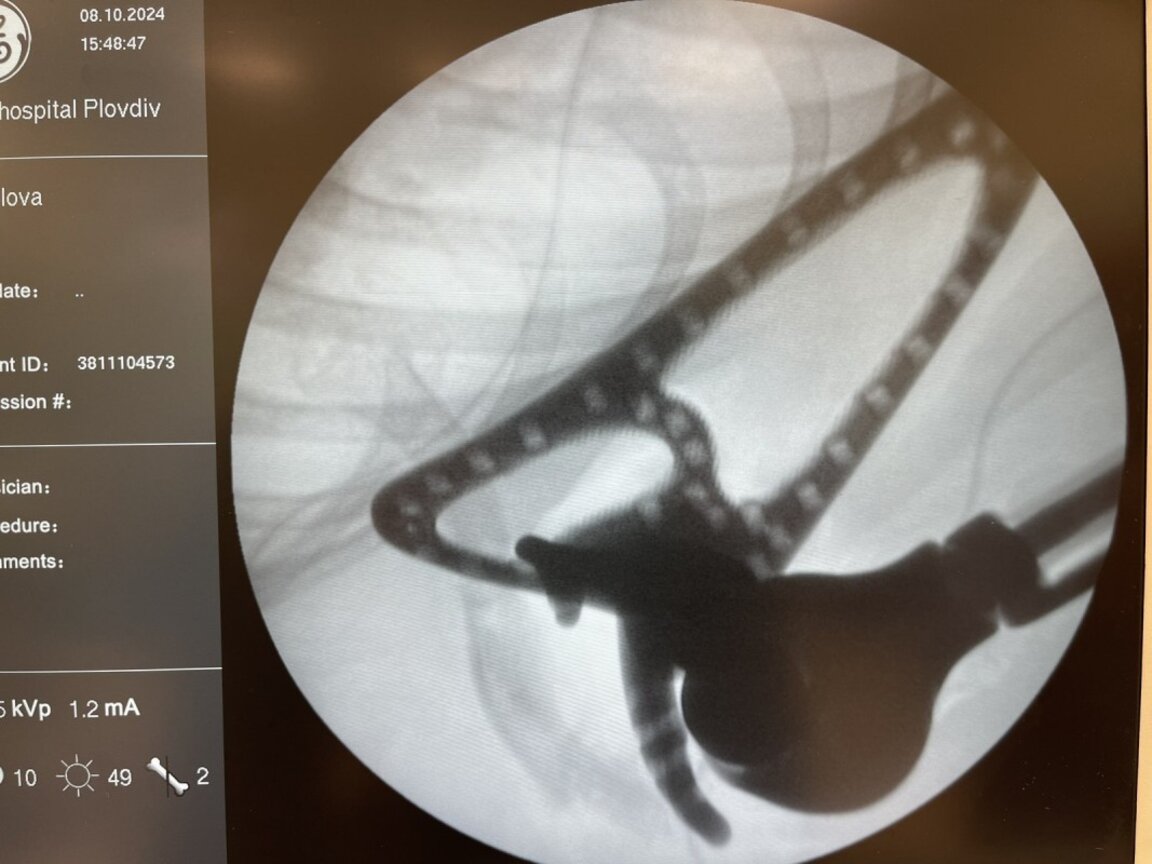

Екипът от водещи хирурзи-ортопеди е отстранил злокачествения тумор чрез тотална резекция премахване на дясната лопатка и горния край на дясната раменна кост на малката пациентка в отделението по ортопедия и травматология на лечебното заведение. Отстранените лопатка и раменна кост хирурзите заместили с 3D принтирана ендопротеза с двойно шарнирана артиколация за рамото, създадена специално за 11-годишното момиче.

Протезата е изработена по индивидуална поръчка за момичето след предварително изготвен скенер с 3D реконструкция. Протезата е от титан, с диамантено покритие и е обвита с текстилна тръба.